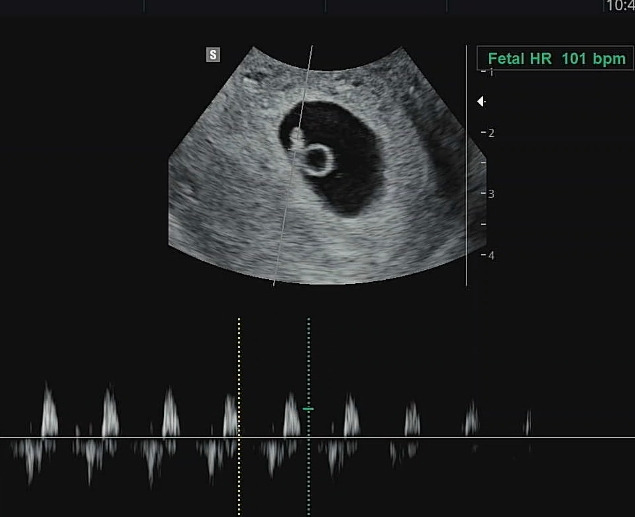

3월 17일 확연히 보이는 난황 + 아기의 형체 확인 (6주 차) 반짝 반짝이는 심장의 모습도 보고 쿵쾅쿵쾅 하는 소리도 들음!!

IMG_0852.heic

IMG_1021.jpg

왼쪽: 5주차 때 사진 / 오른쪽: 6주차 때 - 세로로 길쭉한 게 아기, 동그란 건 난황 - 임신부들 사이에서는 다이아 반지라고 부른다.